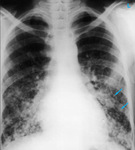

A. Portable upright chest x-ray before aspiration; B. Chest x-ray 1 hour after aspiration, showing bilateral diffuse alveolar infiltrates, worse at the bases on the right side

From the personal collection of Dr S. Murgu and Dr H. Colt, University of California at Irvine Medical Center